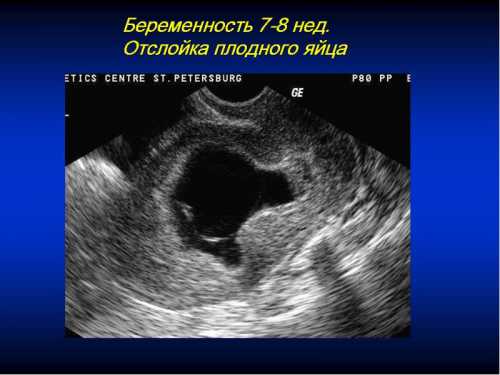

Когда видно плодное яйцо на УЗИ

Опубликовано: 19.1.2019

Кроме этого, уже сейчас у плода формируется нервная трубка, а клетки распределяют между собой обязанности, кто какие органы будет создавать. К концу й недели зародыш уже приобретает свою характерную форму в виде буквы. СВ Читать далее